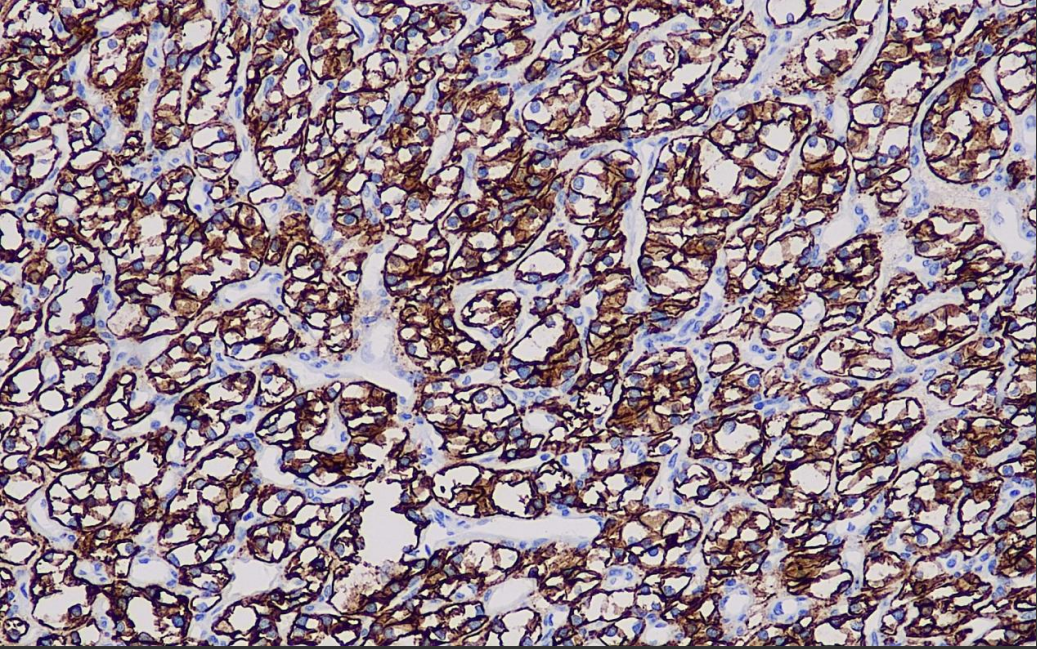

Positive control: renal clear cell carcinoma

Carbonic anhydrase IX is a zinc-containing metalloproteinase that catalyzes the reversal of CO2 hydration by enzyme locking with cell membranes. It is often expressed in the gastrointestinal tract, mainly in the stomach and gallbladder.CA IX is overexpressed in some epithelial malignancies, including the uterus, cervix, lungs, breast, and kidneys, and is not expressed in the corresponding normal tissues.The main role of CA IX is to maintain the extracellular acidic environment and to promote the proliferation of tumor cells.CA IX is used with a sensitivity of 85-100% to differentiate between clear cell renal carcinoma and smoky renal cell carcinoma. It can be used to distinguish renal clear cell carcinoma from smoky renal clear cell carcinoma, and is often used in combination with Pax-2, Ksp-Cadherin, and CD117.CA IX has strong diffuse and multifocal staining in uroepithelial carcinoma, while renal collecting tubule carcinoma is weakly stained, and thus CA IX can distinguish between these two.

CA IX Carbonic Anhydrase 9 Antibody Reagent binds specifically to the CA IX molecular antigen. Immunohistochemistry kits containing CA IX Antibody Reagent are suitable for the precise diagnosis of renal clear cell carcinoma and hypoxia-associated tumors (e.g., cervical cancer, breast cancer).